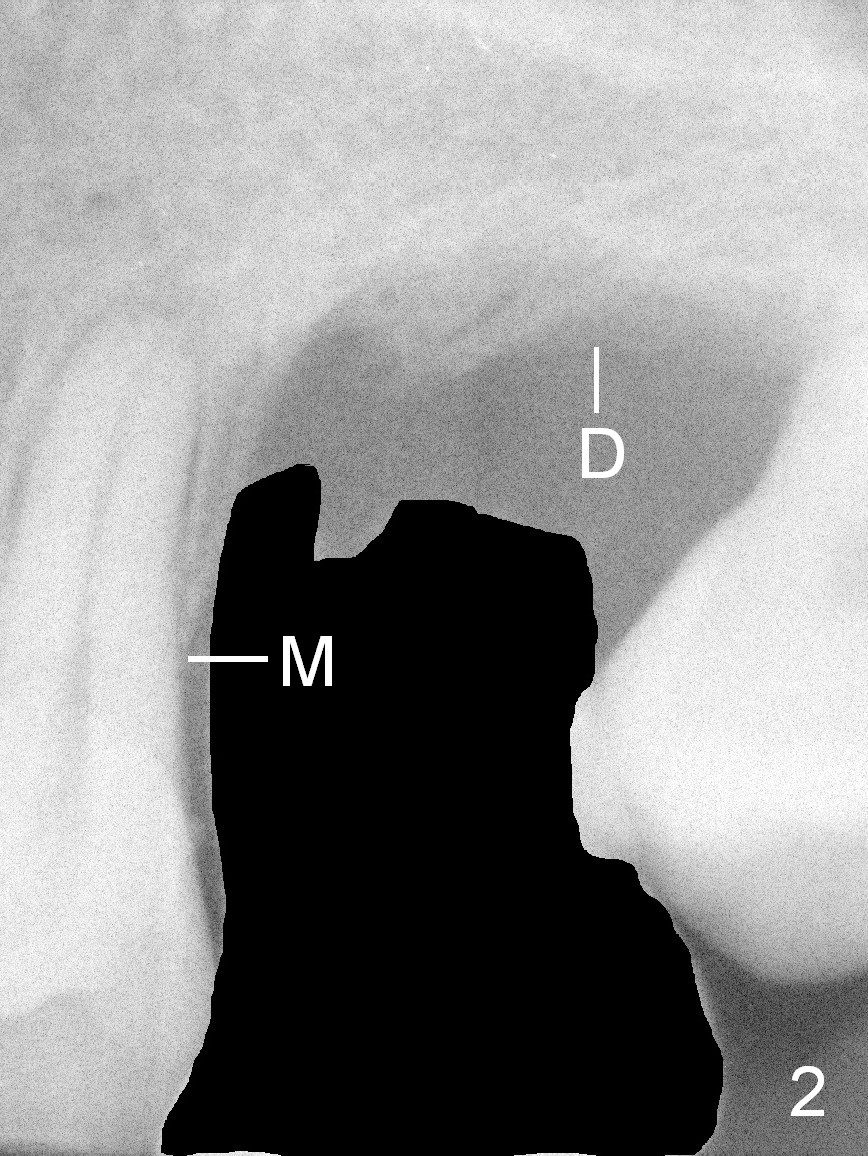

A 42-year-old man (XK) has perio-endo disease at the tooth #14.  After root canal therapy (Fig.1), the tooth remains nonsalvageable.  The bone loss is extensive (Fig.1 *) and uneven (more bone mesially than distally) after extraction (2% Xylocaine/1:50,000 Epinephrine).  A bone-level implant is placed in an ideal depth (Fig.3 UF; Fig.4 SM), irrelevant of the gingival margin, first.   Place bone graft distally (Fig.3 red circles) before choosing a proper abutment.  For example, there is plenty of combination to choose cuff and abutment lengths for a SM or UF implant (Fig.4).